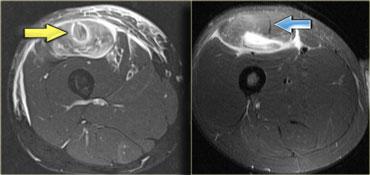

Cấu trúc giải phẫu có thể rất phức tạp.

Ví dụ, ở phía bên trái là cơ thẳng đùi, có thể biểu hiện nhiều dạng phù nề khác nhau tùy thuộc vào vị trí (giải phẫu) của tổn thương.

Mũi tên màu xanh chỉ gân của đầu gián tiếp, xuất phát từ khớp háng, có hướng thẳng đứng trên hình ảnh cắt ngang này.

Dọc theo phần sau của cơ (mũi tên màu vàng), có một vùng gân dẹt xuất phát từ khớp gối.

Khi một cơ có các gân với hướng khác nhau, điều đó có nghĩa là có thể xuất hiện các dạng phù nề khác nhau tùy thuộc vào gân bị tổn thương.

Do đó, đây là dạng phù nề tương ứng với tổn thương xuất phát từ khớp gối.